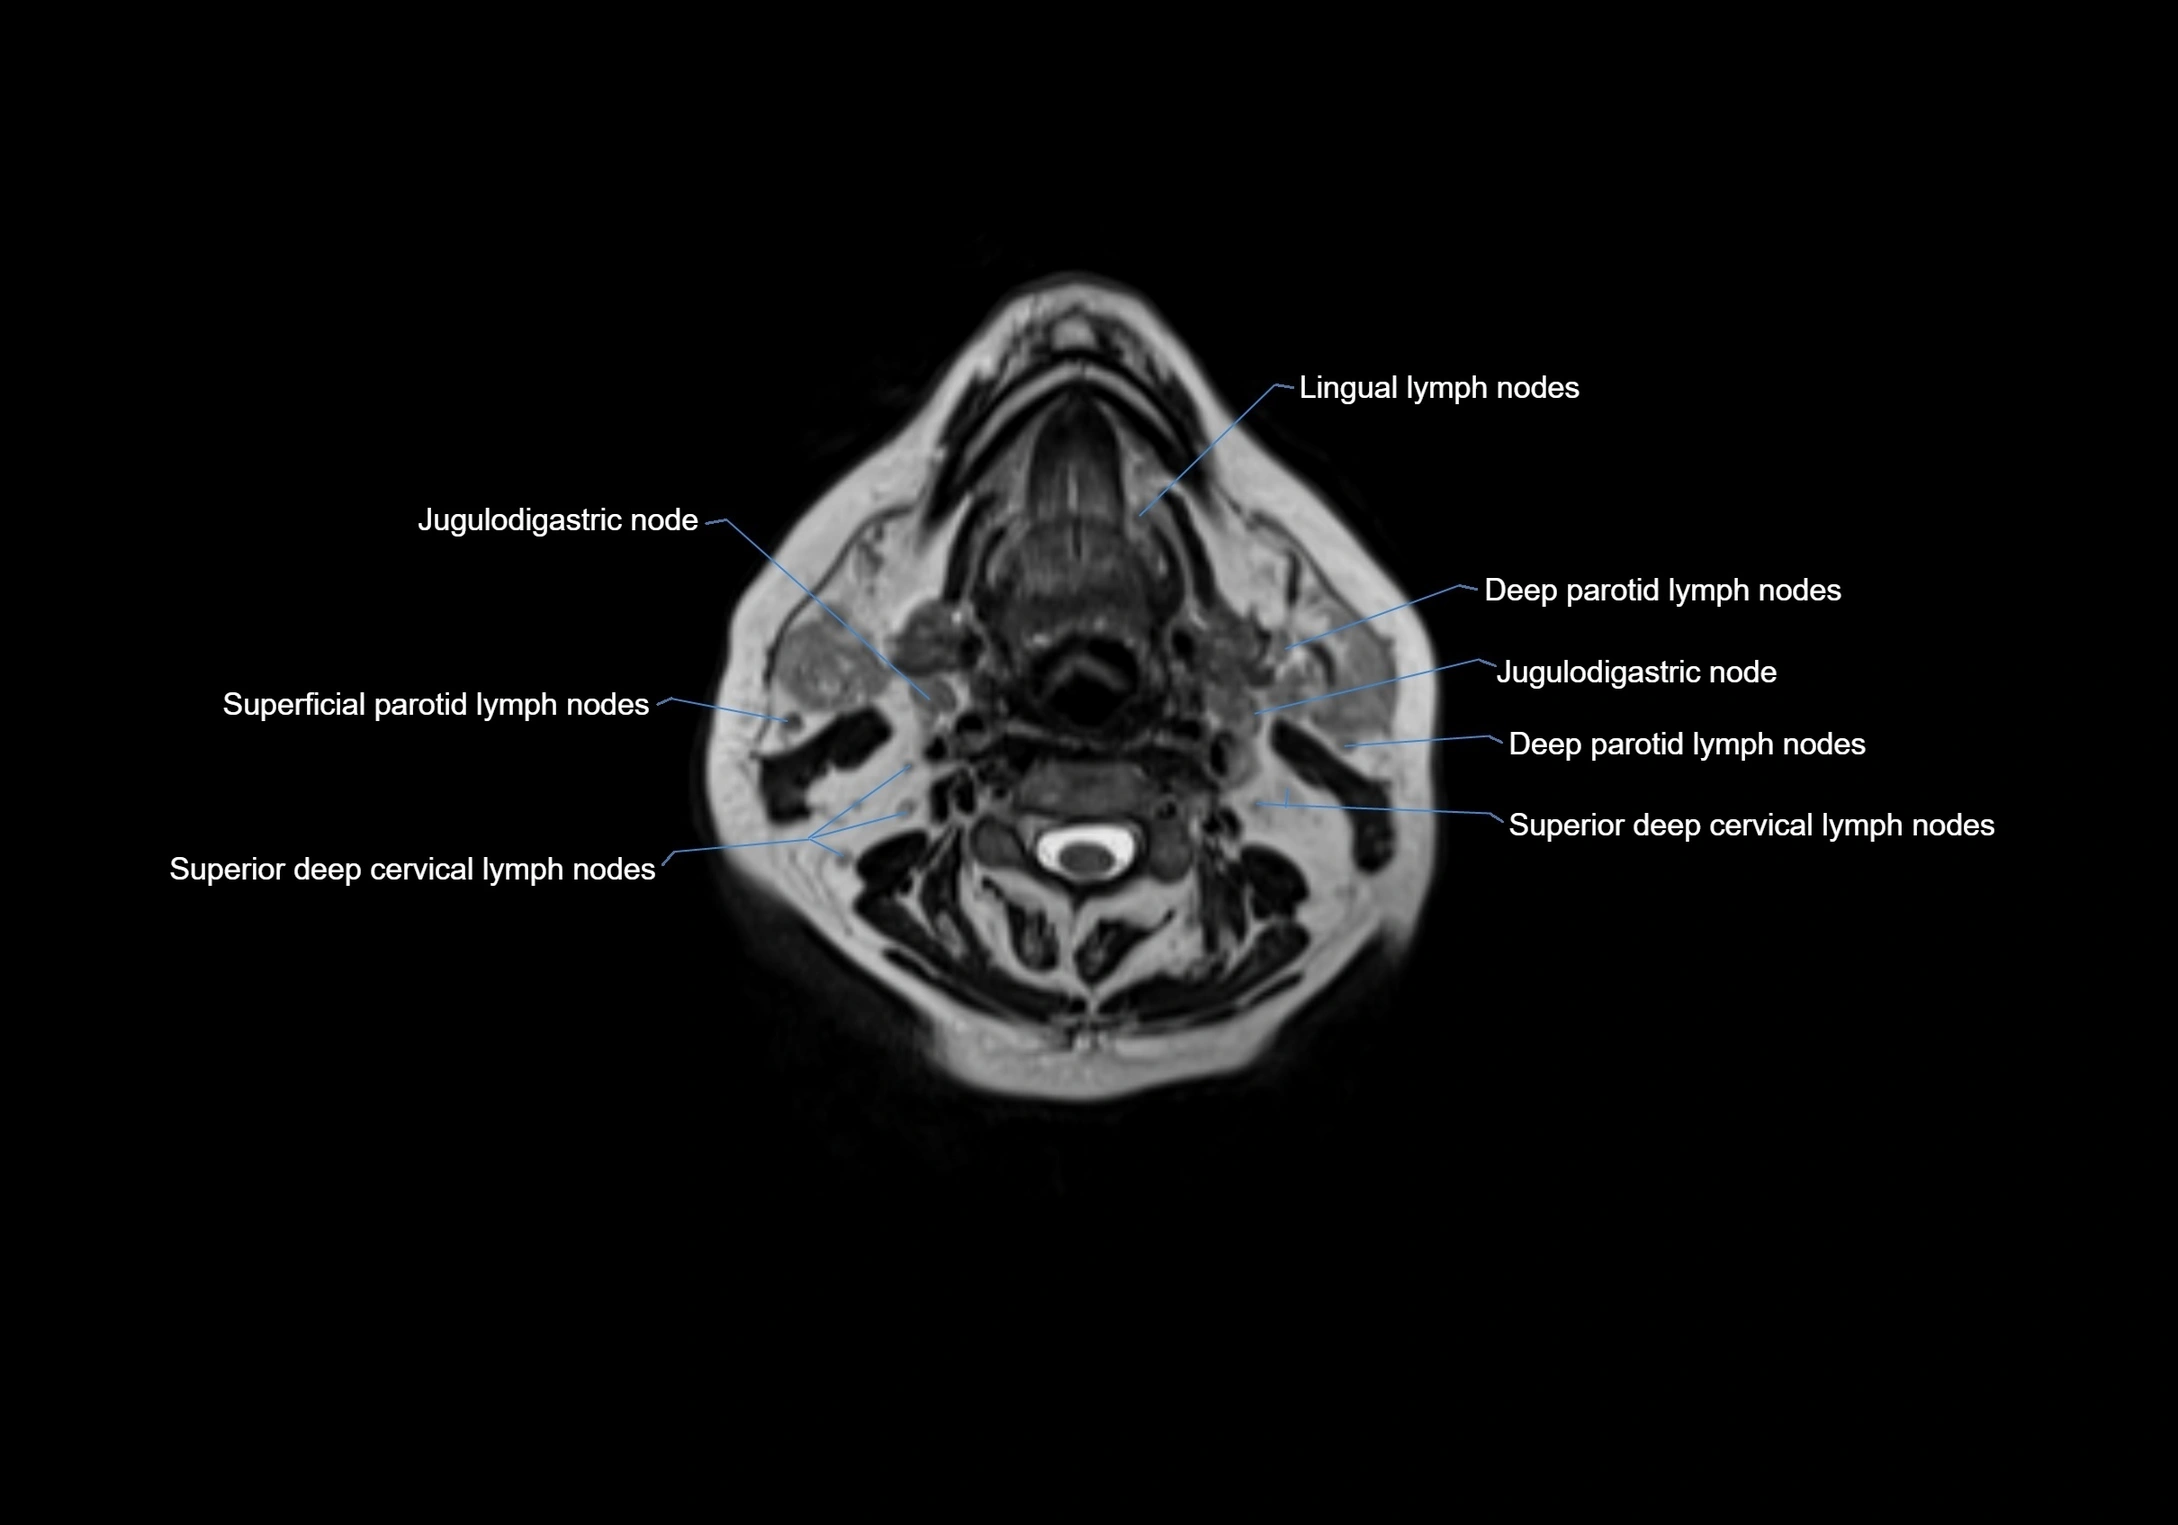

Accessory lymph nodes are small, secondary lymph nodes located along the main facial and cervical lymphatic chains, often adjacent to primary lymph nodes, such as preauricular, submandibular, or occipital nodes. They are typically less than 5 mm in diameter, embedded within subcutaneous fat or connective tissue, and may be variable in number and location. These nodes provide additional filtration and immune surveillance for lymph collected from the face, scalp, and neck regions. Accessory lymph nodes are usually non-palpable in healthy individuals but may enlarge in response to infection, inflammation, or metastasis, making them clinically significant.

Location

• Found along primary lymph node chains, including preauricular, submandibular, parotid, and occipital regions

• Embedded in subcutaneous fat or superficial fascia, often lateral or posterior to primary nodes

• Variable in number; may occur unilaterally or bilaterally, depending on individual anatomy

MRI Appearance

T2-weighted images:

• Nodes show intermediate signal, with surrounding fat bright

• Useful for detecting edema, inflammation, or infiltration

• Fatty hilum may appear slightly hyperintense relative to cortex